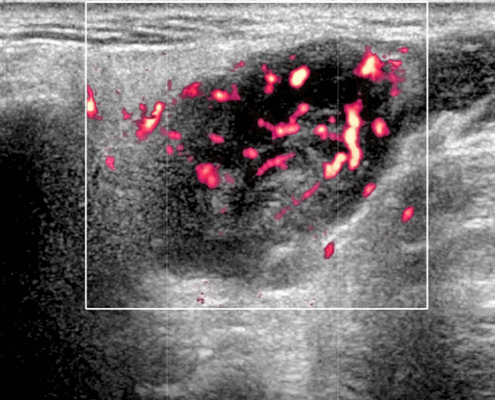

- Отмечается внутренняя васкуляризация на цветном доплеровском исследовании.

- Цветной допплер. Внутриузловая васкуляризация от умеренной до выраженной